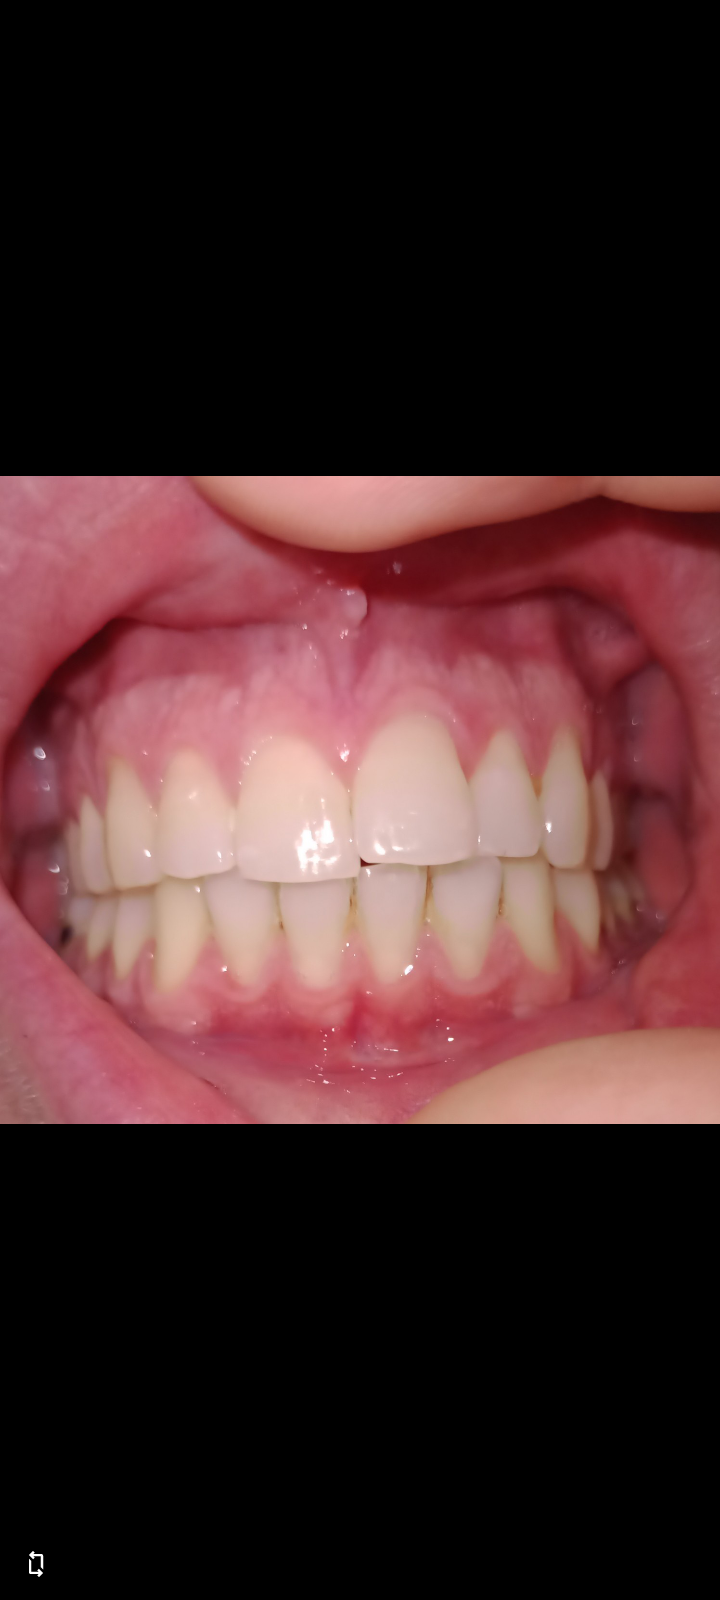

Sono così affollati? Le recessioni ci sono davvero?

Buongiorno, è possibile chiedere un consiglio? Ho ricevuto più opzioni di cura diverse, il primo dentista mi diceva che non serve l'apparecchio, non soddisfatta del mio sorriso mi rivolgo al secondo e propone estrazione di tre premolari (di cui uno con trasposizione del canino) e chiudere lo spazio di un molare estratto.